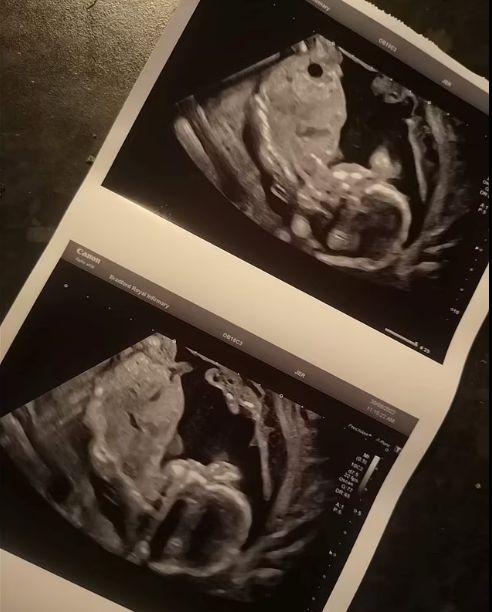

27-годишната Хана Коул била приета в болница в 20-ата седмица от бременността, откакто водите й ненадейно изтекли. По време на прегледа лекарите не съумели да засекат сърдечния темп на бебето и назначили на пациентката изкуствено раждане.

В последна сметка се оказало, че предчувствията на британката са правилни и при втория обзор лекарите разкрили сърдечния темп на плода. Те се извинили за грешката си и траяли да наблюдават положението на пациентката.